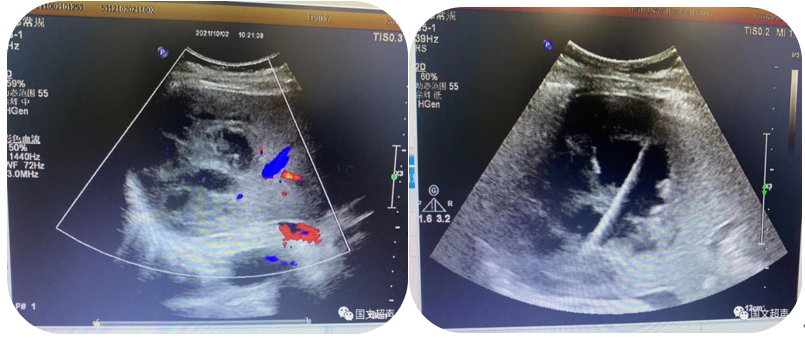

3.超声引导下经皮经肝胆道置管引流、胆囊造瘘;经皮肾造瘘、膀胱造瘘

超声实时引导下将引流管放置在因肿瘤、结石等压迫、堵塞梗阻扩张的胆道、肾盂、胆囊、膀胱内引流出潴留的胆汁、尿液,防止或缓解肝肾功能衰竭,进而减缓患者痛苦为临床争取治疗机会。

经皮经肝胆囊造瘘、胆道置管引流

经皮肾造瘘

经皮膀胱造瘘